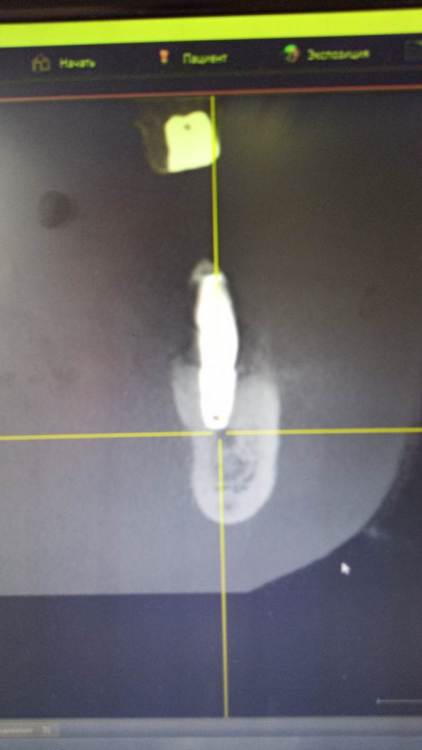

Зндрю Опубликовано 2 февраля, 2024 Автор Поделиться Опубликовано 2 февраля, 2024 (изменено) КТ имеется . Окончание импланта лежит на нижней ветви тройничного нерва, но не травмирует его. Со слов независимого имплантолога, у которого был на консультации, иначе симптомы были бы неврологические , а их нет . Изменено 2 февраля, 2024 пользователем Зндрю Ссылка на комментарий

kramer Опубликовано 7 февраля, 2024 Поделиться Опубликовано 7 февраля, 2024 В принципе понятно. Лично мое мнение, что надо удалять оба имплантата (ближний выглядит недозаглубоенным (плохо видно), дальний слишком близко к нерву, что скорее всего и дает симптомы. Установить новые импланты, сделать мостовидную конструкцию. Ссылка на комментарий